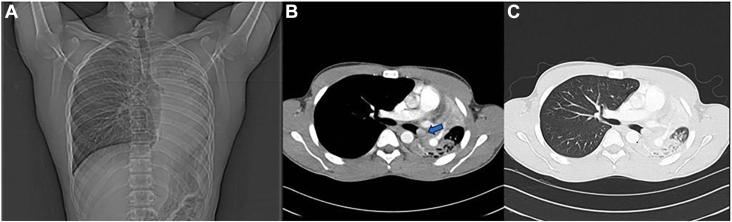

Inflammatory myoblastic tumors of the lung are rare benign lesions. Here we present the case of a 15-year-old boy with postobstructive pneumonia. Computed tomography of the chest revealed a mass in the left mainstem bronchus that was confirmed on bronchoscopy. A rigid bronchoscopy with core resection was performed. Findings on pathologic examination were consistent with an inflammatory myoblastic tumor. The initial core resection relieved his postobstructive pneumonia; however, repeat bronchoscopy a month later demonstrated recurrence of the lesion. The tumor was removed with a parenchymal-sparing sleeve resection. At 80 months of follow-up, the patient is without evidence of recurrence or stenosis.

肺炎性肌纤维母细胞瘤是罕见的良性病变。在此,我们报告一例15岁患有阻塞性肺炎的男孩。胸部计算机断层扫描显示左主支气管有一肿块,支气管镜检查证实了这一情况。进行了硬质支气管镜下的核心切除术。病理检查结果与炎性肌纤维母细胞瘤相符。最初的核心切除术缓解了他的阻塞性肺炎;然而,一个月后复查支气管镜显示病变复发。采用保留实质的袖状切除术切除了肿瘤。在80个月的随访中,患者没有复发或狭窄的迹象。